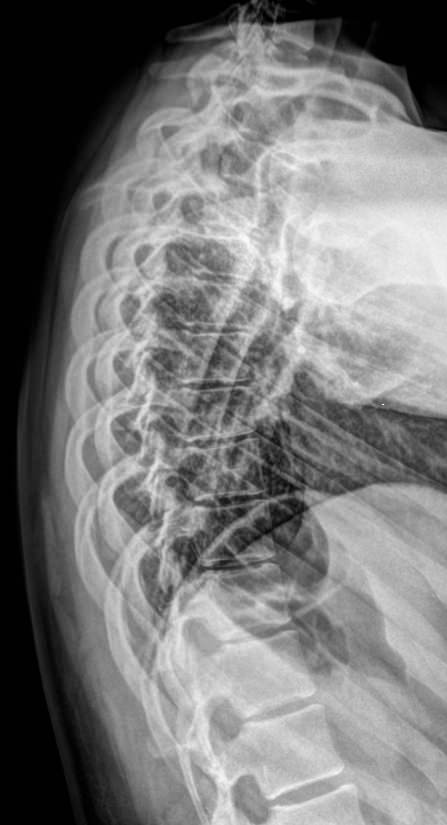

Рентгеновское исследование ― один из основных видов диагностики и первое, что назначают при подозрении на патологию грудного отдела позвоночника. На снимки попадают: 7-й шейный и все 12 грудных позвонков, а также частично ребра и ключицы. Диагностика всегда выполняется в 2 проекциях. Костные образования отчетливо видны и дают возможность определить патологические изменения и назначить необходимое лечение.